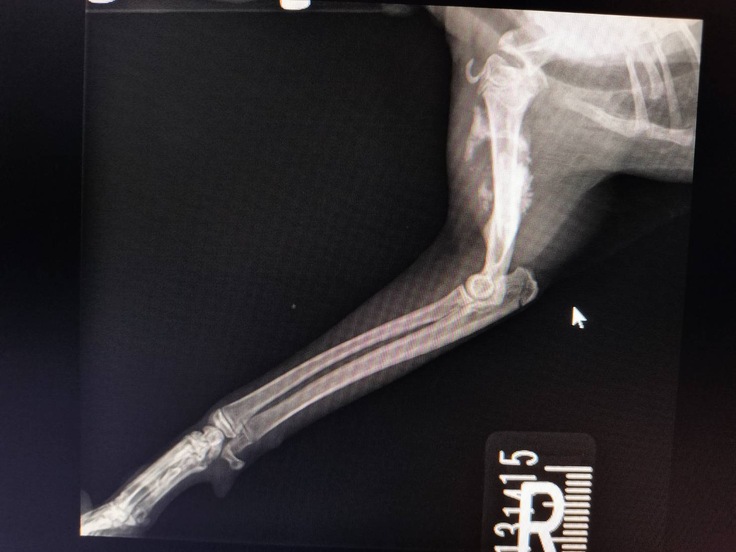

骨は大丈夫…

ボッキリ折れた大腿骨

すでに骨がずれたまま、くっつき始めてる